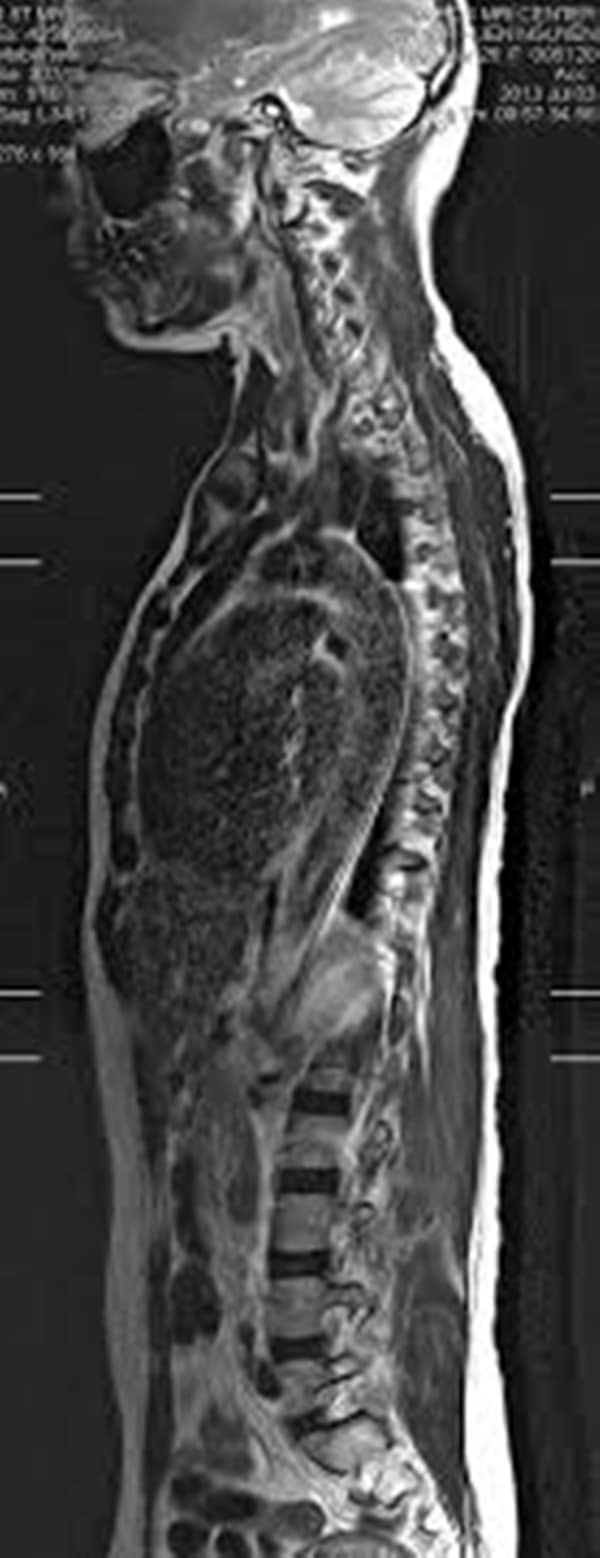

Για να πούμε τη διαφορά και για τη διάγνωση της νευροσαρκοείδωσης, οι γιατροί κάνουν μία ή περισσότερες από τις ακόλουθες εξετάσεις

- Η αξονική τομογραφία